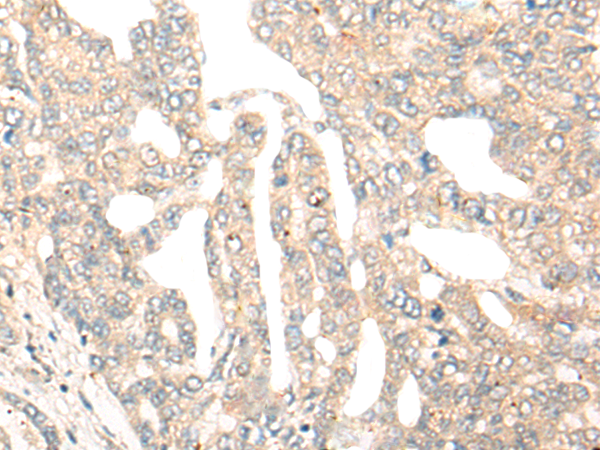

IHC positive control: |

Human thyroid cancer and Human esophagus cancer |